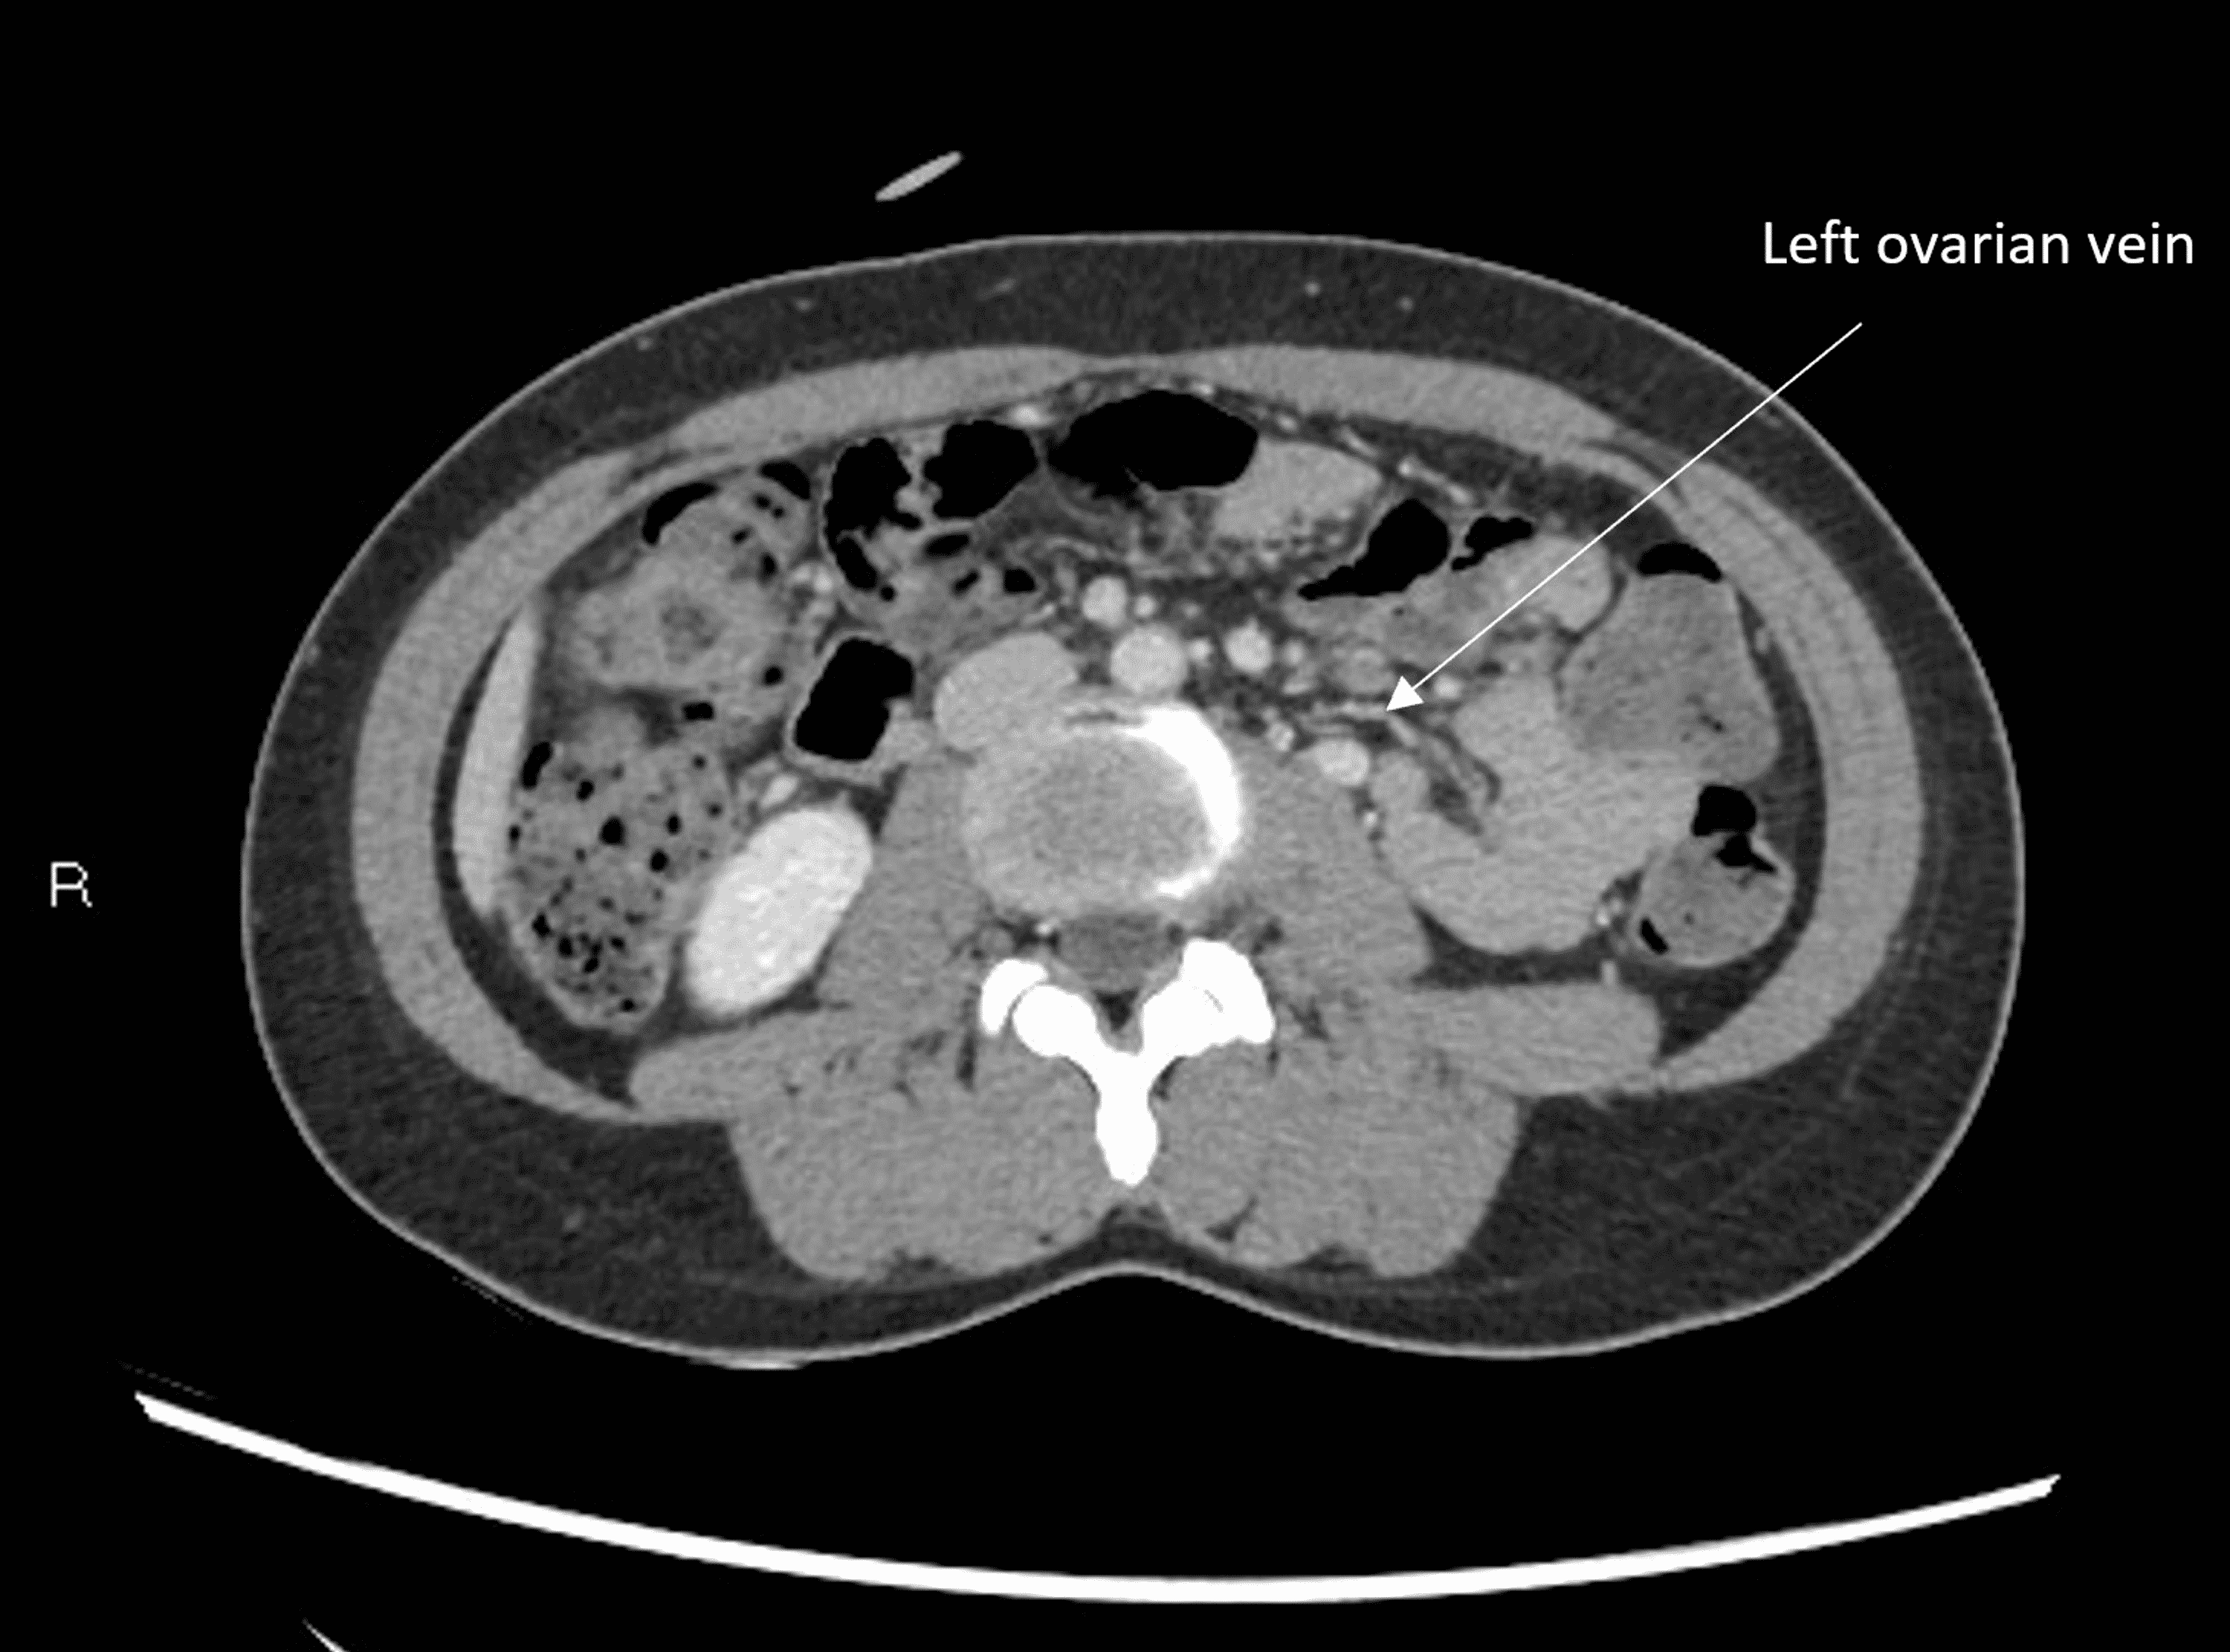

From radiopaedia.org

Nutcracker syndrome (annotated CT) Image Nutcracker Syndrome Pain Often, patients have had several emergency room visits for pain. This can restrict blood flow, which may lead to symptoms such as left flank pain and blood and protein. These symptoms are due to the left. Patients most commonly present with unexplained hematuria and flank or pelvic pain, which can be severe at times. Nutcracker syndrome (ns) is a condition. Nutcracker Syndrome Pain.